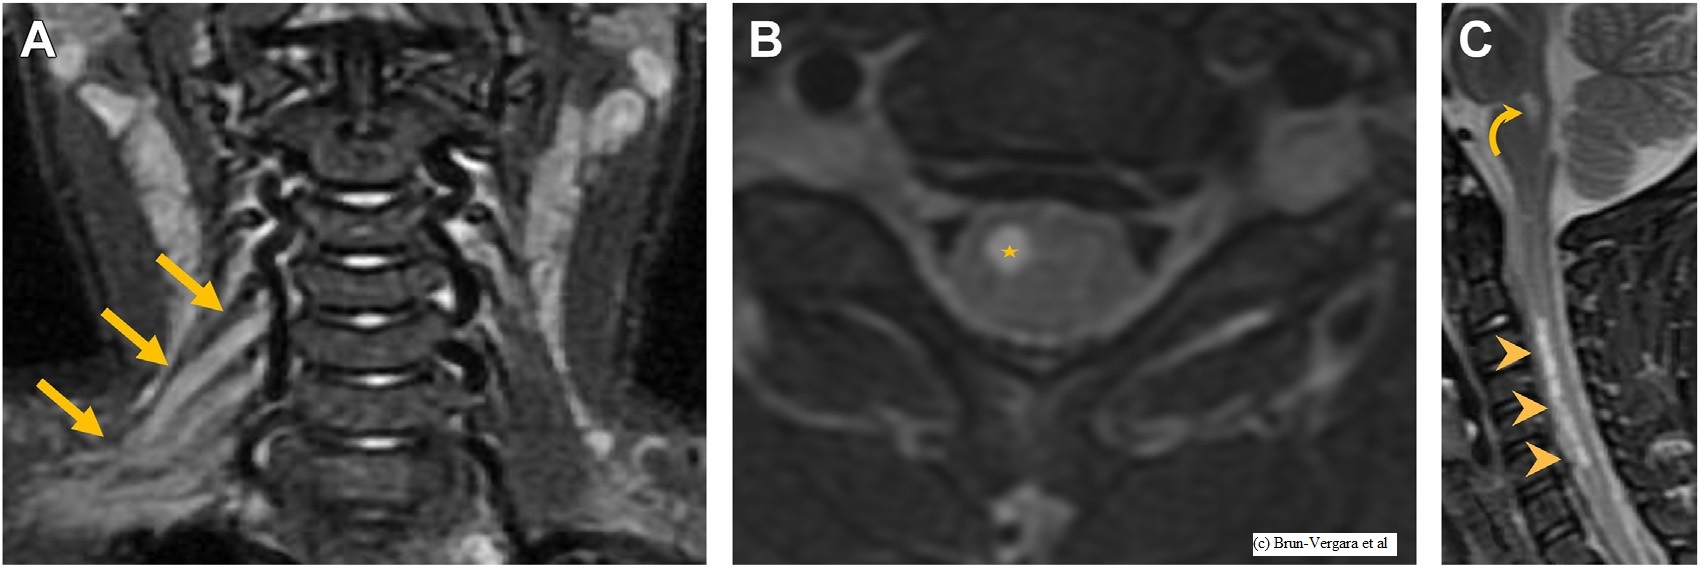

EBNA1 titers are elevated in radiologically isolated syndrome and correlate with cognitive impairment

Erandi Munasinghe

Koroboshka Brand-Arzamendi

Timothy Lim

Lisa Eunyoung Lee

Melanie Guenette

Suradech Suthiphosuwan

Aditya Bharatha

Jiwon Oh

Raphael Schneider

Background

Epstein-Barr virus (EBV) infection is believed to be a critical prerequisite for the development of multiple sclerosis (MS). This study aims to investigate whether anti-EBV titres are elevated before the onset of MS symptoms in people with radiologically isolated syndrome (pwRIS) and to evaluate their association with cognitive impairment.

Methodology

EBV antigen titers were quantified in a cohort of 37 pwRIS, 50 people with MS (pwMS), and 24 healthy controls (HC) using Enzyme-Linked Immunosorbent Assay (ELISA). Cognitive function of pwRIS were assessed using Minimal Assessment of Cognitive Function in Multiple Sclerosis (MACFIMS).

Results

Anti-EBV Antibody Responses Across MS Subtypes and RIS

Figure 1

Figure 1. Anti-EBV antibody titers in HC, pwRIS, relapsing-remitting MS (pwRRMS), and primary progressive MS (pwPPMS). (A) Viral capsid antigen (VCA) IgG titers and (B) Epstein–Barr nuclear antigen 1 (EBNA1) IgG titers were measured by ELISA. *p < 0.05 with Mann-Whitney U test.

Anti-EBV Antibody Titers in Relation to Global Impairment

Figure 3

Figure 2. Anti-EBV antibody titers in patients with or without global impairment. (A) VCA IgG titers and (B) EBNA1 IgG titers measured by ELISA. *p < 0.05 with Mann-Whitney U test.

Association Between EBV Antibody Levels and Cognitive Function

Figure 4 1

Figure 3. Correlation of EBNA1 IgG Titers with Minimal Assessment of Cognitive Function in Multiple Sclerosis (MACFIMS) Scores. Scatter plots showing the correlation between EBNA1 IgG titers and Z-scores from (A) Brief Visuospatial Memory Test (BVMT), (B) California Verbal Learning Test (CVLT), (C) Judgment of Line Orientation (JOLO), and (D) Symbol Digit Modalities Test (SDMT). The correlation coefficient (r) and p-values (P) were assessed using Spearman rank correlation.

Figure 4 2

Figure 3. (E–H) Scatter plots showing the correlation between EBNA1 IgG titers and Z-scores from (E) Paced Auditory Serial Addition Test 2-second version (PASAT2), (F) PASAT 3-second version (PASAT3), (G) Delis-Kaplan Executive Function System - Color-Word Interference Test: Condition 3 (DKEFS CS), and (H) DKEFS - Design Fluency: Condition 1 (DKEFS DS). The correlations were assessed using Spearman rank correlation.

Conclusions

Elevated EBNA1 titers are detectable prior to MS symptom onset and are associated with cognitive function of pwRIS. However, their role in disease progression and clinical outcomes require further investigation.